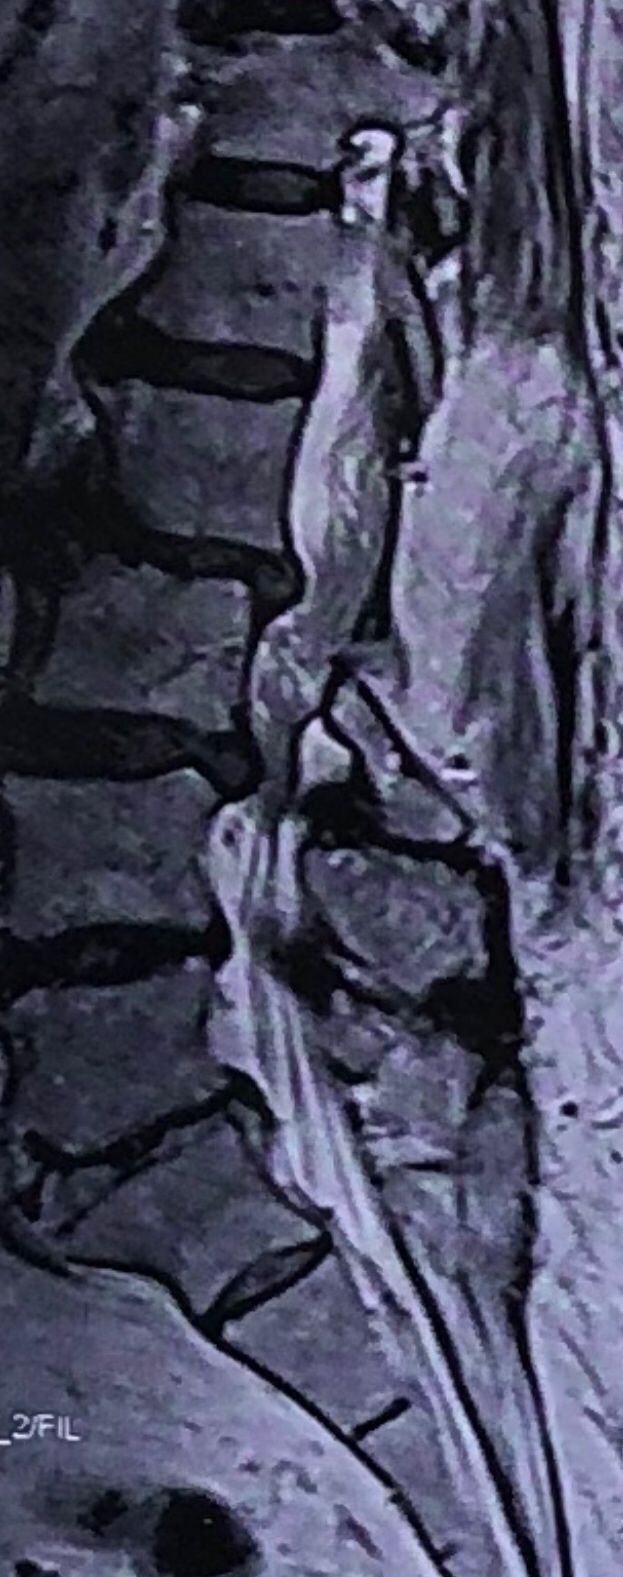

70 yrs old female presented to my clinic today (Oct 06/2024)due to severe LBP with both legs pain for several years.

7 years ago came to my clinic with L leg radicular pain and I referred her to a neurosurgeon. Patient underwent full laminectomy from L1 to S1. Few months after surgery her LBP and legs pain were started and hasn’t improved since then. Now walking aggravates the pain and forces her to bend forward. Patient had mri from 6 months ago. Her mri 7 years ago was similar to the recent mri, just laminectomy and soft tissue collection has been added. In neurological examination p.tvdid not have any neurological deficits. I ordered lower limbs emg/ncv, dynamic lumbar spine X.ray. As a chiropractic Doctor what would be your plan of management for this patient?